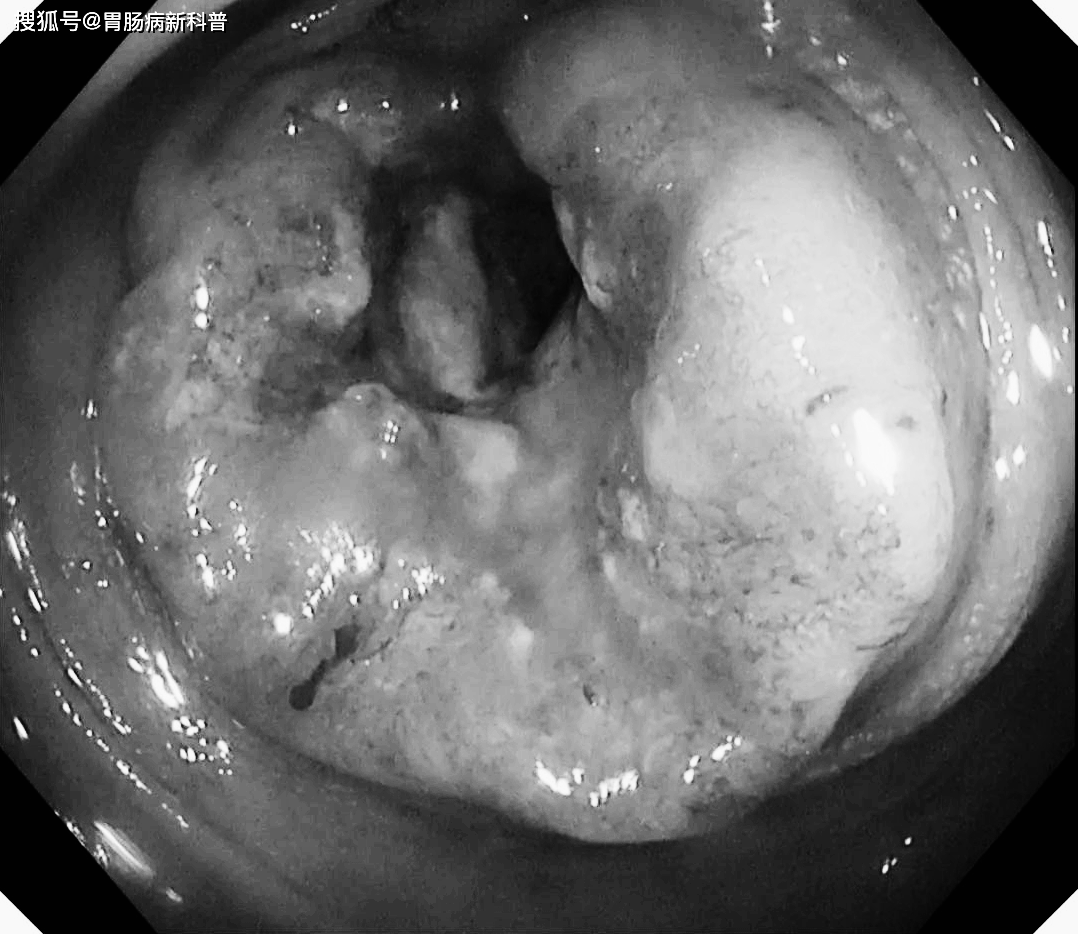

54岁的梁先生,告诉我们他患痔疮十多年,大便偶尔带血,吃几天药也见效,其他没啥感觉,就在近半年,症状加重,蹲便时出血呈喷射状,人也消瘦了不少。

结果肠镜检查发现直肠癌。

距肛门25—28cm处,巨大肿物,肠镜勉强通过,病理确诊为结肠癌。